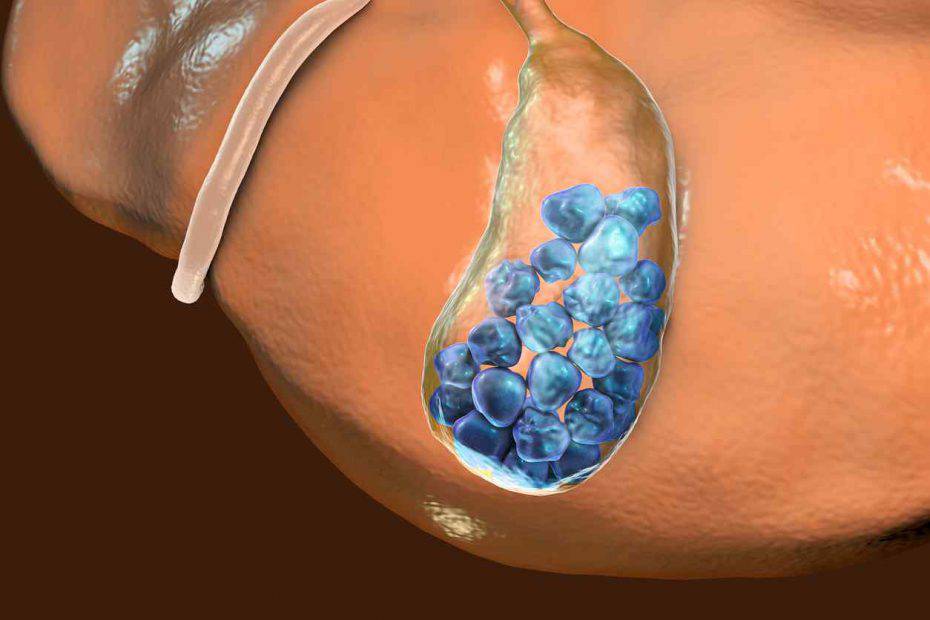

I calcoli biliari sono come dei sassolini che si formano nella colecisti e possono essere grandi come un granellino di sabbia oppure una pallina da ping pong. In sostanza, si tratta di cristalli che si accumulano nella colecisti. Nel caso avvertiate sintomi come dolore durante l’ispirazione profonda, coliche addominali, nausea e vomito, sappiate che è bene rivolgersi ad uno specialista che possa darvi rimedi efficaci e adatti al vostro particolare caso.